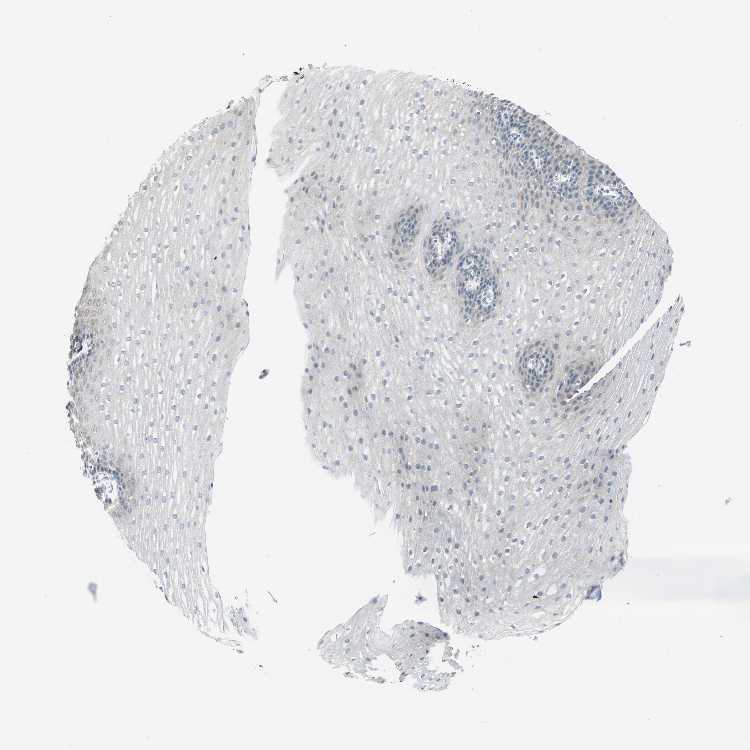

ESOPHAGUS - Antibody stainingi

Antibody staining in the annotated cell types in the current human tissue is reported as not detected, low, medium, or high, based on conventional immunohistochemistry profiling in selected tissues. This score is based on the combination of the staining intensity and fraction of stained cells.

Each image is clickable and will lead to virtual microscopy that enables deeper exploration of all samples and also displays staining intensity scores, fraction scores and subcellular localization as well as patient and tissue information for each sample.

Antibody HPA029759Antibody HPA029760Antibody CAB004998

Squamous epithelial cells MediumNot detectedNot detected